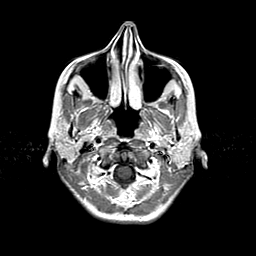

Metastatic bronchogenic carcinoma: T1-weighted MR -- Slice #0

[Home][Help][Clinical] Slice 0